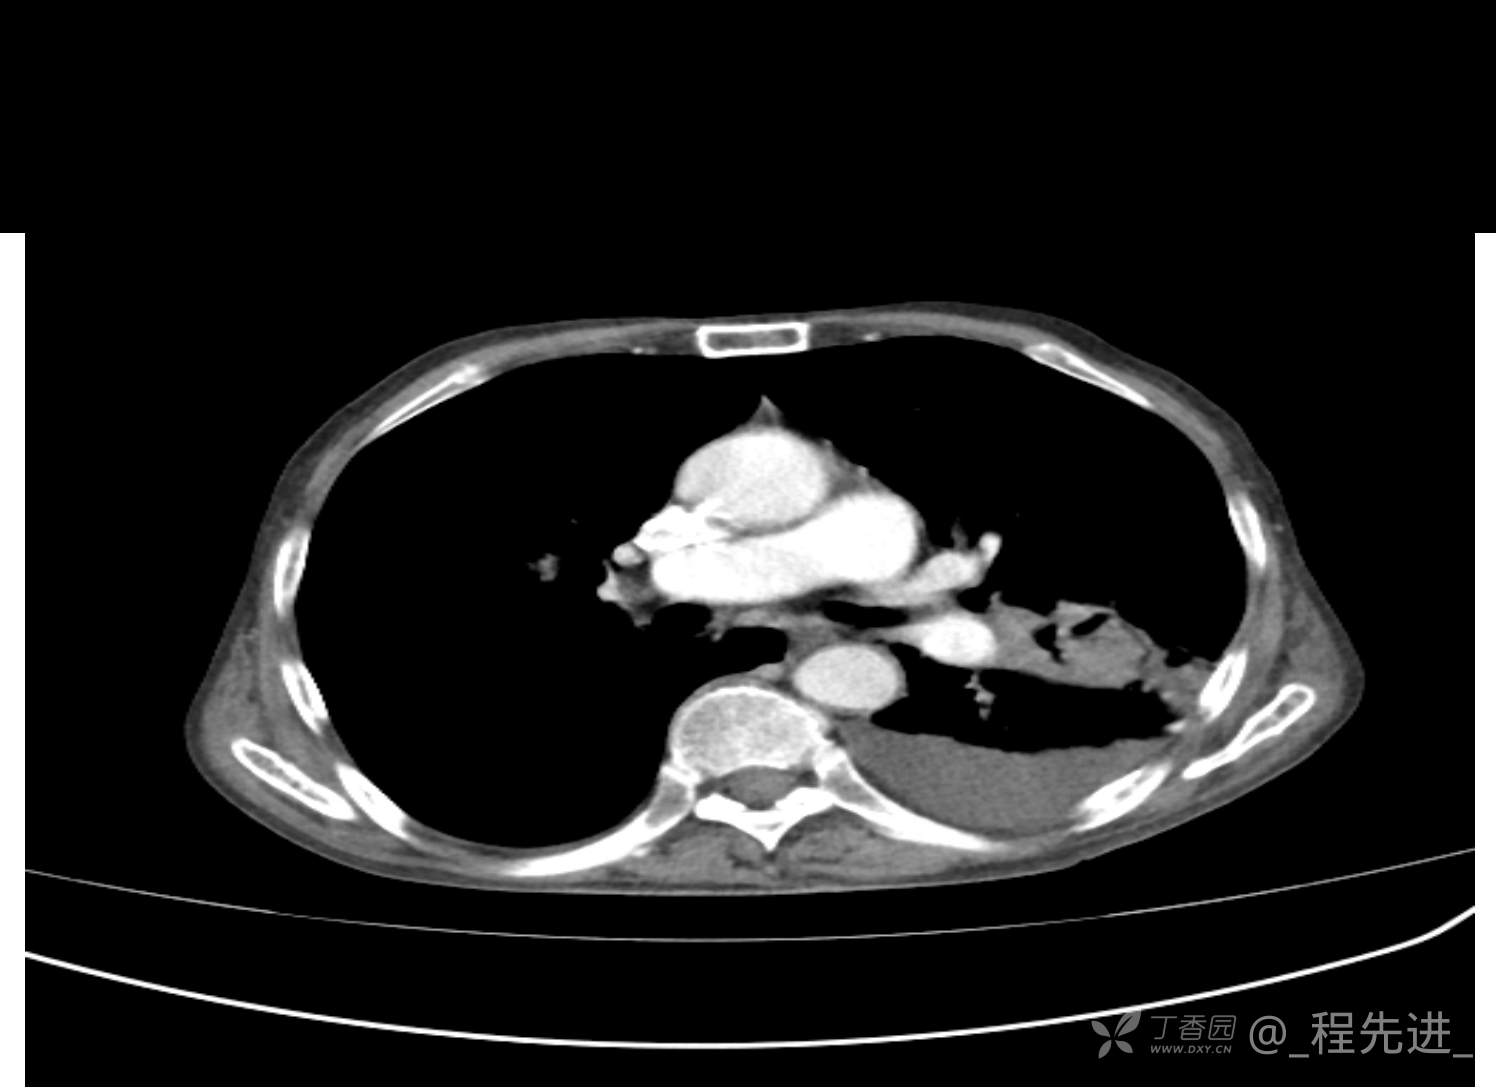

患者性别:男

患者年龄:81岁

简要病史:反复咳嗽、咳痰20余年,加重1周。两肺呼吸音低,可闻及散在干湿啰音。